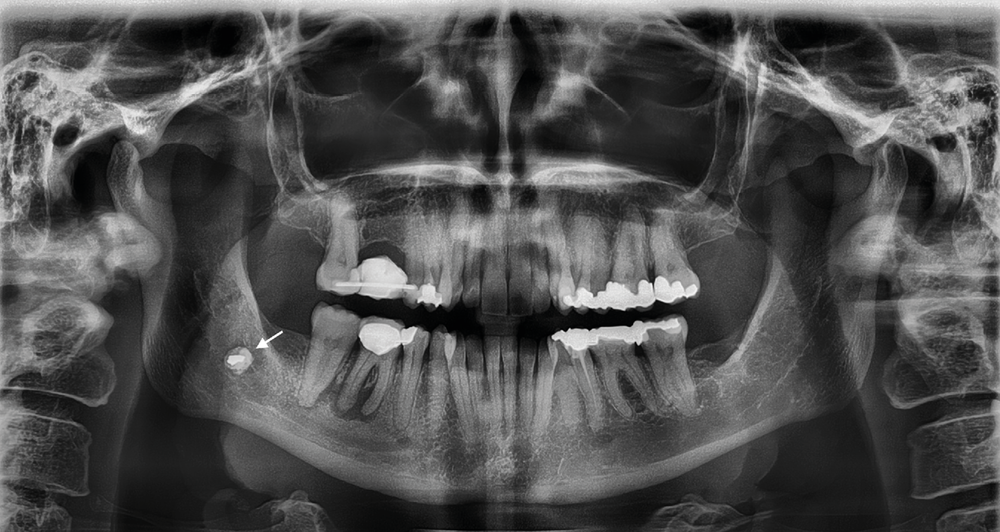

1a-c. Cette femme de 49 ans souffrait depuis des années de fortes douleurs et d’engourdissements dans la région du menton droit suite à l’extraction des dents de sagesse. a. La panoramique indique la présence d’une structure osseuse au niveau de l’angle mandibulaire droit.